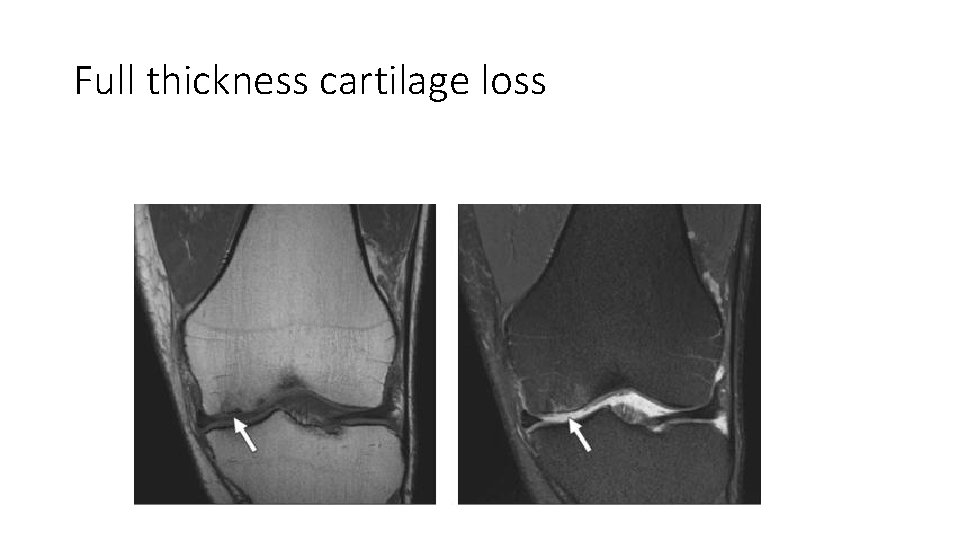

Full thickness cartilage loss

Grade 4 chondral thinning to bone of the medial tibial plateau (arrows) greater than to adjacent medial femoral condyle